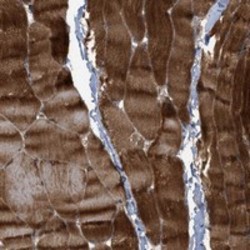

- Experimental details

- Immunohistochemical staining of human skeletal muscle with ABRA polyclonal antibody (Cat # PAB20958) showed strong cytoplasmic positivity at 1:50-1:200 dilution.

- Validation comment

- Immunohistochemistry (Formalin/PFA-fixed paraffin-embedded sections)